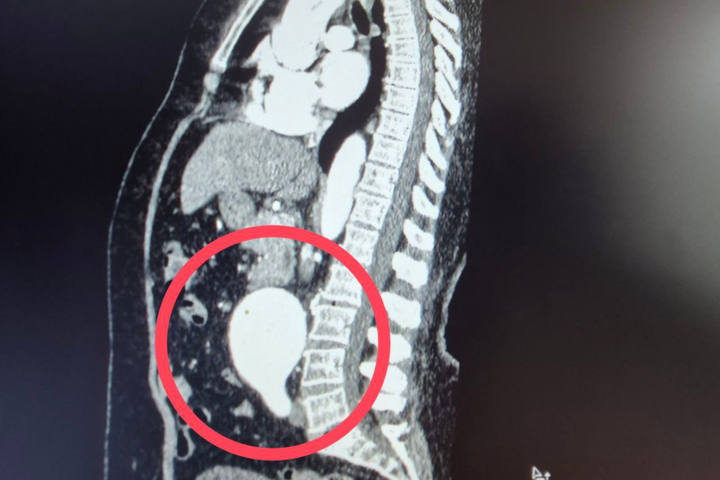

Как пояснили медики, к ним поступила 60-летняя пациентка с крайне опасным диагнозом — мешотчатая аневризма брюшной аорты.

«Это патологическое расширение главного сосуда организма, которое в любой момент может привести к внутреннему кровотечению. Случай действительно уникальный — аневризма брюшной аорты считается «бомбой замедленного действия», а мешотчатая форма особенно опасна из-за риска мгновенного разрыва.

Ситуация была настолько серьезной, что в проведении операции женщине отказали даже в областных клиниках», — пояснили в больнице.